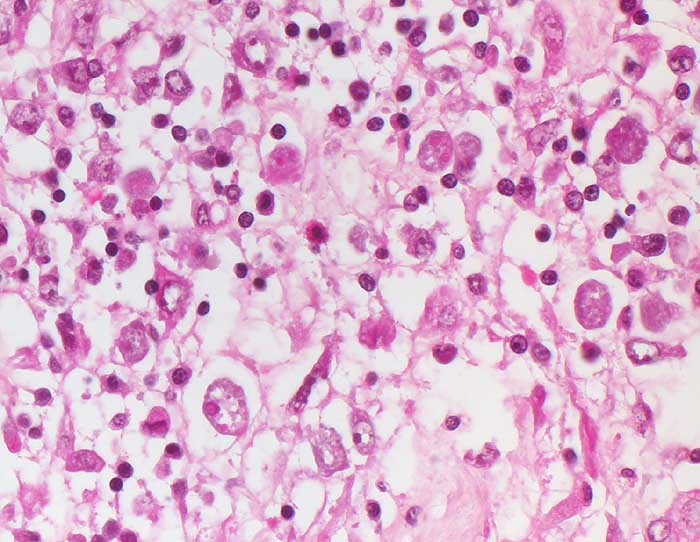

PathoPic – image database / PathoPic ID 6463 - Amöbiasis

Amöbiasis

Rundliche gewebsinvasive Magnaform von Entamoeba histolytica mit rundem Kern und phagozytierten Erythrozyten im Gewebe am Rand des Ulkus.

Die gewebsinvasiven Throphozoiten bewirken an der Schleimhautbasis eine Histolyse an der Grenze zur Muscularis mucosae unter Ablösung der Schleimhaut. Bei 90-99% der Infizierten verläuft der Infekt asymptomatisch (intestinale Darmlumeninfektion mit Erregerausscheidung). Die restlichen Patienten leiden an einer invasiven Amöbiasis. Die Krankheit kommt vor allem in den Tropen und Subtropen, seltenerweise aber auch in Mitteleuropa vor. Es gibt ein vegetatives Stadium der Trophozoiten und Zysten, die aus bis zu vier Trophozoiten gebildet werden. Im Dünndarm werden aus ingestierten Zysten Trophozoiten freigesetzt in Form von apathogenen Kommensalen, der Minutaform (12-18 Mikrometer) und der histolytischen Magnaform (bis 20-30 Mikrometer) mit Erythrophagozytose. Die Freisetzung proteolytischer Enzyme bewirkt eine Kolliquationsnekrose. Bei chronischer Ulzeration entwickelt sich ein Amöbom bestehend aus Granulationsgewebe, das den Darm einengen und ein Karzinom imitieren kann. Häufigste Komplikation ist der Leberabszess.

Histologie

400